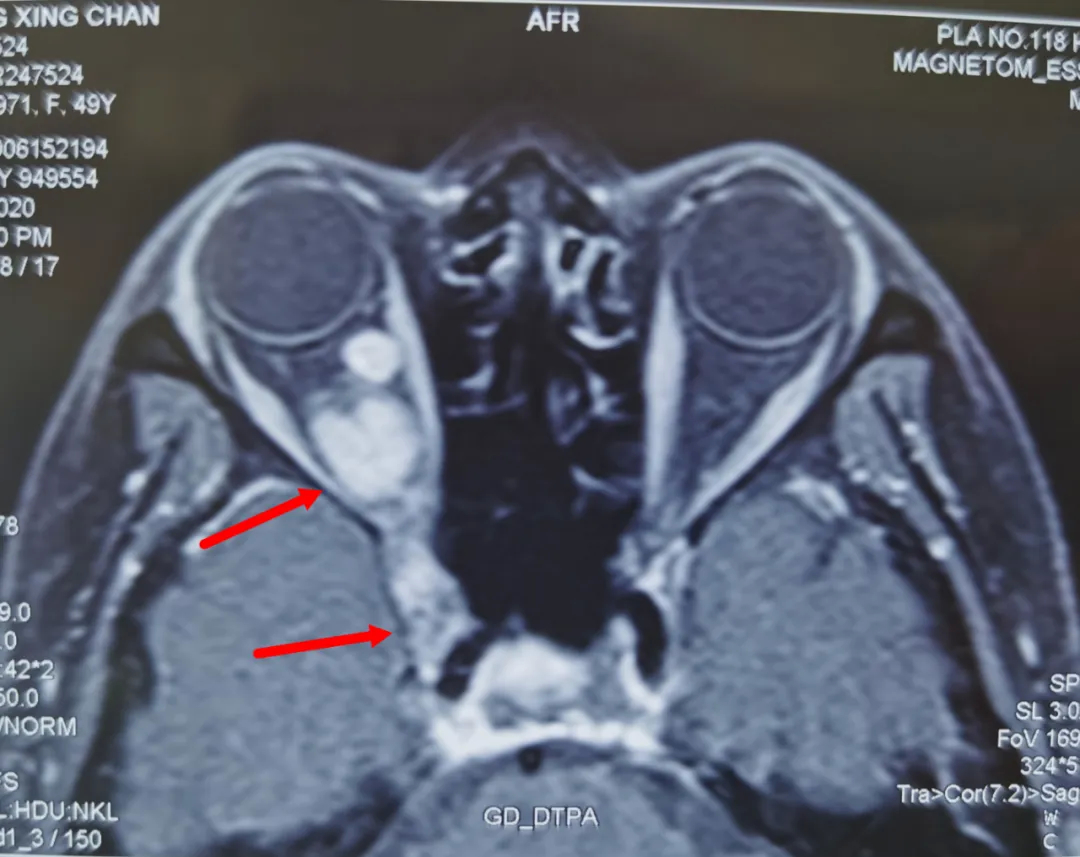

上月中旬,邓女士来到温医大附属眼视光医院。经过吴文灿仔细检查,发现肿瘤已牢牢占据眼眶深部,并通过眼球后方的眶上裂蔓延至颅内。眶上裂是除视神经外绝大部分颅内神经进入眼眶的唯一通道,肿瘤压迫此部位的神经,才导致多年的眼痛和头痛。

更严重的是,肿瘤已到达颅内最大的血库——海绵窦的深部,与颈内动脉紧紧相贴。照此发展下去,患者不仅将失去视力,甚至影响脑部功能危及生命。

患者的头部水平核磁共振图片,箭头处为肿瘤。画面上方为眼眶,下方为颅脑。肿瘤横跨两处。